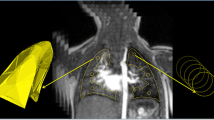

A comparison of the DMD-based perfusion maps and the DCE-based TWIST perfusion map is provided in Fig. 5 for a patient with left-sided herniation with ECMO therapy. Additionally, ventilation maps obtained with DMD MRI are also displayed. For both methods, the reduction of perfusion values in the ipsilateral lung can be observed visually and quantitatively.

Representative magnitude images from bSSFP protocols, along with normalised perfusion, and fractional ventilation maps obtained through DMD MRI from a patient with left-sided hernia and ECMO therapy (patient no. 5). Additionally, a representative magnitude image and PBF map obtained from DCE-based TWIST protocol for the same patient from a similar slice location are displayed. For visualisation purposes, all functional maps are cropped to the region of interest. Overall, reductions in the ipsilateral lung can be observed visually, and can be confirmed by the resulting quantitative ratios (displayed overlaid on functional maps). Although the TWIST-based method can generate quantitative PBF maps, DMD MRI does not require the administration of contrast agents and is also capable of generating ventilation maps

Pearson’s correlation and Bland–Altman analyses between QRatio and PBFRatio are visualised in Fig. 6. Correlation coefficients are \(r=0.89,p<0.01\) for Protocol A, and \(r=0.90,p<0.01\) for Protocol B, indicating very strong correlations between QRatio and PBFRatio for both protocols. Bland–Altman plots demonstrate a close agreement between QRatio and PBFRatio, with reproducibility coefficient (RPC) \(RPC=0.22\) for Protocol A, and \(RPC=0.20\) for Protocol B, and without a significant bias (\(p>0.05\)) or systematic difference for both protocols.

Pearson’s correlation and Bland–Altman analyses between perfusion ratios obtained via DCE-based TWIST (PBFRatio) and DMD MRI (QRatio) for (a) Protocol A and (b) Protocol B. For both protocols, we observe a very strong correlation without any significant bias or systematic difference. (r, Pearson’s correlation coefficient; RPC, reproducibility coefficient.)